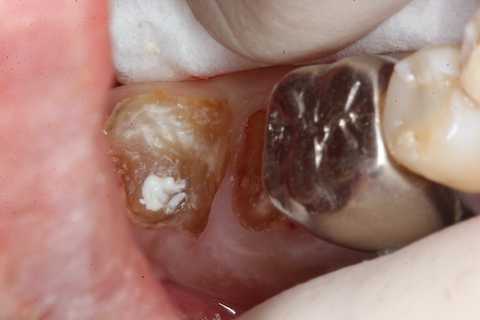

今日も野戦病院シリーズ26(CK破折) 2025.10.25